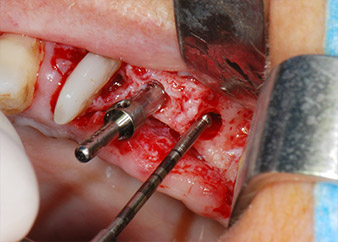

Vor der Insertion der Implantate wurde infiziertes Weichgewebe im Implantationsbereich und um das Abutment mit einem Instrument entfernt, das laut Hersteller primär zur Knochenbearbeitung und zum Sammeln von Knochenspänen vorgesehen ist (Piezomed, Einsatz B5) (Abb. 6 und 7).